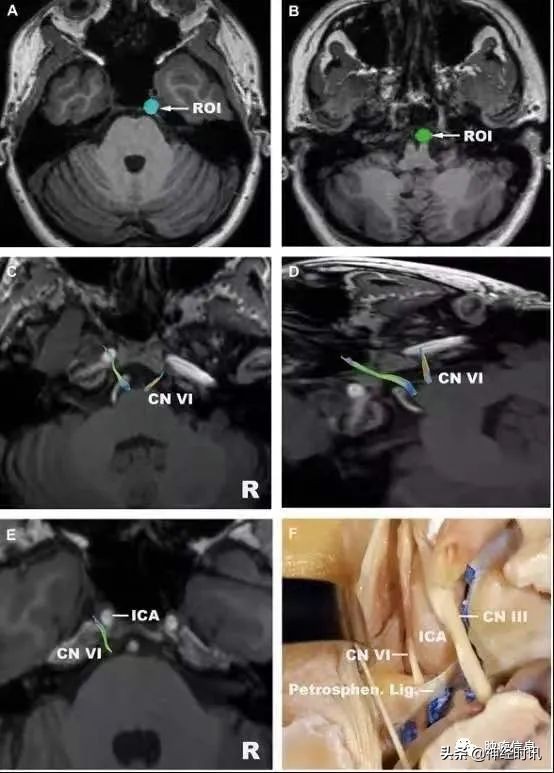

上图 :外展神经。

A,感兴趣区选在 Dorello 入口处;

B,感兴趣区选在脑桥延髓沟处;

C,高分辨率示踪外展神经;

D,斜位观察外展神经;

E,外展神经高分辨率示踪局部观;

F,对应的解剖示意图。

ICA,颈内动脉;

Petrosphen.Lig.,蝶岩韧带